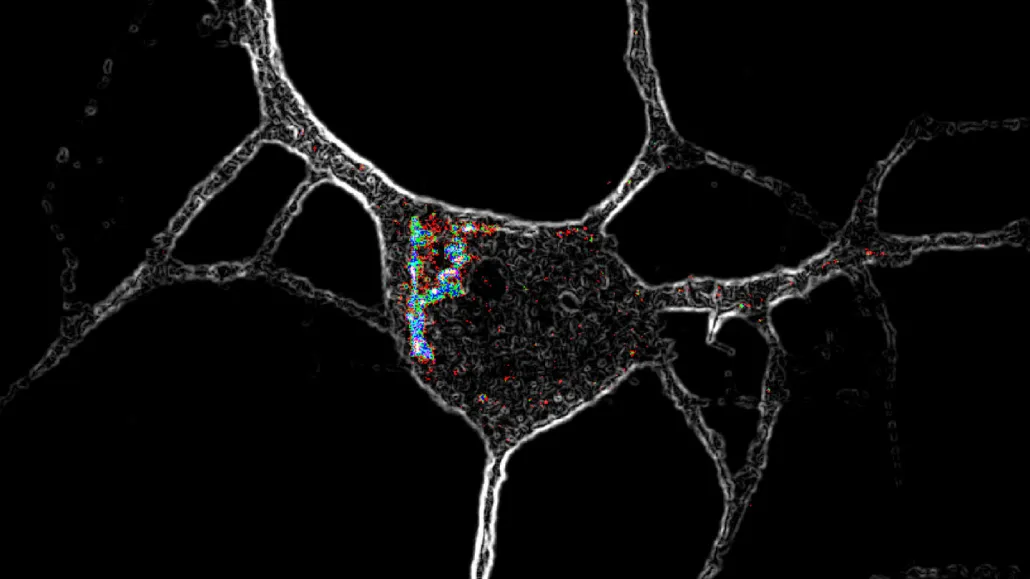

Psychedelic chemical compounds like LSD activate special receptors (highlighted with colors in this microscope image) located inside nerve cells, causing the neurons to grow.

David Olson/UC Davis